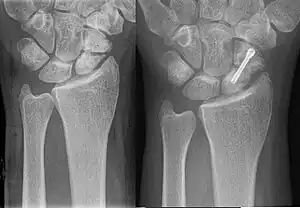

Hypertrophic nonunion

In a hypertrophic nonunion, the fracture site contains adequate blood supply but the fracture ends fail to heal together.[6] X-rays show abundant callus formation. This type of nonunion is thought to occur when the body has adequate biology, such as stem cells and blood supply, but inadequate stability, meaning the bone ends are moving too much. Typically, the treatment consists of increasing stability of the fracture site with surgical implants.[7]